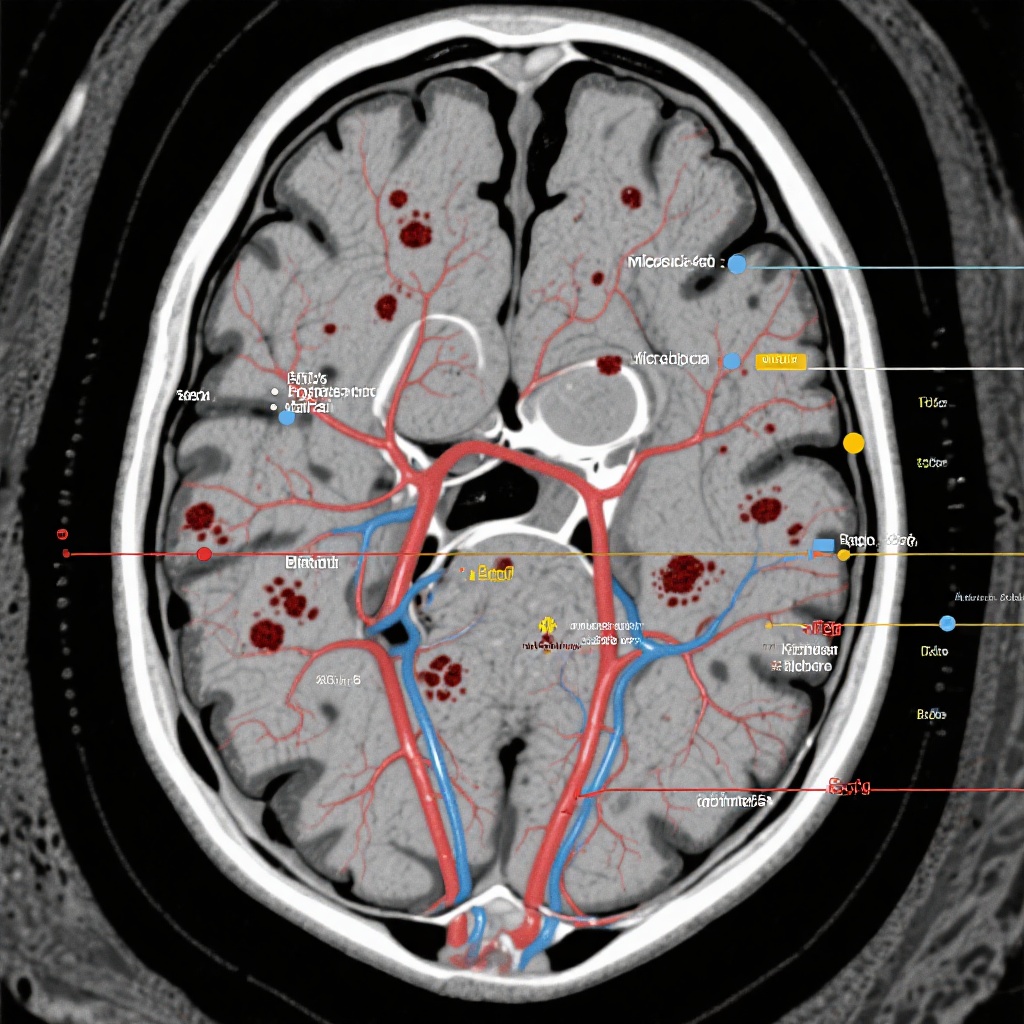

Two experienced raters, who were entirely blinded to the treatment assignments, independently evaluated the MRI scans. The primary radiologic end points for this specific analysis were:

- Incident Intracranial Hemorrhage (ICH): Defined as a bleeding event greater than 10 mm in diameter.

- Cerebral Microbleeds (CMBs): Defined as small, rounded areas of signal void on susceptibility-weighted imaging (SWI) or T2*-weighted gradient-recalled echo (GRE) sequences, measuring 10 mm or less.

- Cortical Superficial Siderosis (CSS): Characterized by linear residues of blood products in the subarachnoid space or superficial layers of the cerebral cortex.

The results indicated no statistically significant differences in the development of new hemorrhagic lesions between the apixaban and aspirin groups. The specific findings were as follows:

1. Intracranial Hemorrhage (>10 mm)

Incident ICH occurred in 5.1% of patients in the apixaban group compared with 6.4% in the aspirin group. The slight numerical difference favored apixaban, though it did not reach statistical significance (P > .05).

2. Cerebral Microbleeds (≤10 mm)

The development of new microbleeds was observed in 7.8% of the apixaban group and 10.8% of the aspirin group. Again, there was no evidence that anticoagulation with apixaban led to a higher burden of small-vessel hemorrhagic markers compared to standard antiplatelet therapy.

3. Cortical Superficial Siderosis (CSS)

Incident CSS, often a marker of cerebral amyloid angiopathy or previous subarachnoid hemorrhage, was found in 7.7% of the apixaban group and 12.9% of the aspirin group. This finding is particularly noteworthy as CSS is a strong predictor of future symptomatic ICH, and the lack of an increase in the apixaban group supports its safety profile.